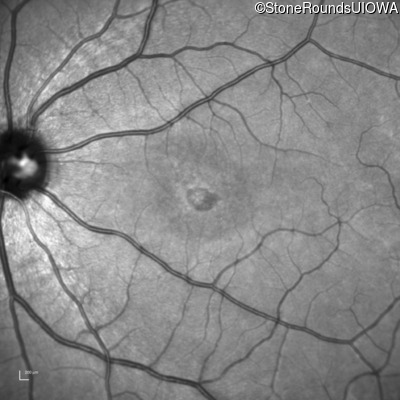

Age at visit: 17 years

OD OS

This 17 year old female first noted problems with her visual acuity around age 13 when she had trouble seeing the projector from the back of the classroom.